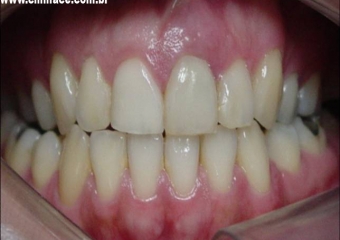

Sorriso final do caso terminado em julho de 2009

Prótese fixa em porcelana instalada